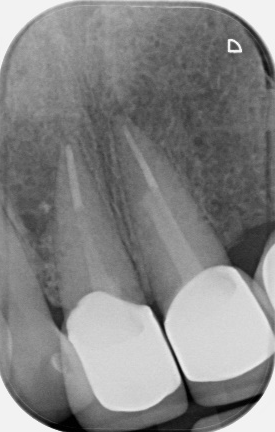

Dental trauma management

Pre-operative photo and X-ray

6 month review